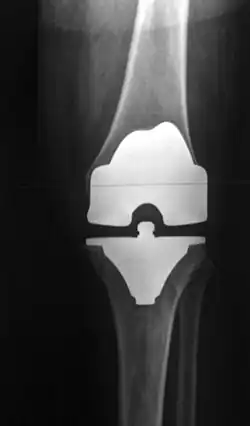

Knieprothese

Eine Knieprothese, Knieendoprothese oder Kniegelenksprothese ist eine implantierte Prothese (Endoprothese), die das Kniegelenk ganz (als TEP = Totalendoprothese) oder teilweise ersetzt. Die Knieprothese wird hauptsächlich bei schwerem Verschleiß des Knies (Kniegelenksarthrose = Gonarthrose, Pangonarthrose) und nach Verletzungen des Knies als operative Therapie eingesetzt, um die schmerzfreie Bewegungsfähigkeit und gegebenenfalls bei Bandinstabilitäten zusätzlich auch die Kniegelenksstabilität wiederherzustellen. Es können Teil- oder Totalendoprothesen (als Halb- oder Ganzgelenke) verwendet werden. Die Knieprothese ist nach der Hüftgelenksprothese die am zweithäufigsten verwendete Gelenksendoprothese mit deutschlandweit jährlich etwa 175.000 Erst-Operationen (Erstimplantationen 2009).[1]

Bei den primären Totalendoprothesen erfolgt eine Einteilung der Prothesen in der Regel danach, ob die Kreuzbänder erhalten werden, dann wird eine CR-Prothese (cruciate retaining ‚Kreuzband-erhaltende Prothese‘) eingesetzt. Sind die Kreuzbänder nicht erhalten oder werden sie im Rahmen der Operation entfernt, wird eine Prothese verwendet, die die Funktion der Kreuzbänder teilweise übernimmt. Dies ist eine PS-Prothese (posterior stabilised ‚posterior stabilisierte Prothese‘). Diese führt das Schienbein bei zunehmender Beugung nach vorne bzw. den Oberschenkelknochen nach hinten.

Für den Drehgleitmechanismus gibt es dabei drei Verfahren, die jedes ein anderes Design der Tibiakomponente haben, während Femur- und Patellakomponente gleich bleiben:

- Die Tibiakomponente besteht ausschließlich aus Polyethylen, und dieses wird mittels Knochenzement direkt auf den präparierten Schienbeinknochen gesetzt (all-polyethylene).

- Eine Polyethylenkomponente wird fest fixiert auf eine Metallkomponente aufgesetzt, die wiederum im Schienbein entweder mit oder ohne Zement verankert wird (modular metal backed oder fixed bearing).

- Eine Polyethylenkomponente wird so auf eine Metallkomponente aufgesetzt, dass sie sich in einem vorgegebenen Rahmen gegen die Metallkomponente bewegen kann, was vorwiegend ein Gleitmechanismus bei Kniebeugung ist (rotating platform oder mobile bearing). Die Metallkomponente wird wiederum zementiert oder unzementiert im präparierten Schienbeinknochen fixiert.